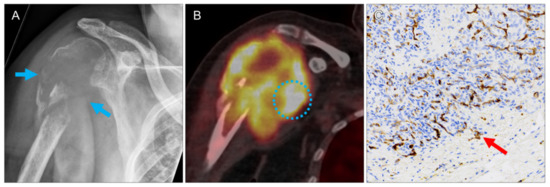

| 2 | lung, right upper lobe | 0.7 | 0.2 | 1.2 | 0.8 | 1.5 | 0 | ccRCC | 2 | 2 | 2 | 2 |

| 4 | lung, right lower lobe | 1.5 | 1.8 | 2.8 | 1.8 | 2.5 | 1 | ccRCC | 3 | 4 | 2 | 2 |

| 5 | lung, left lower lobe | 1.1 | 0.7 | 1.7 | 1.3 | 2.8 | 1 | ccRCC | 2 | 3 | 2 | 2 |

| 6 | lung, right upper lobe | 1.0 | 0.5 | 4.2 | 2.9 | 5.3 | 1 | ccRCC | 4 | 2 | 3 | 2 |

| 8 | lung, right lower lobe | 1.1 | 0.7 | 3.1 | 2.0 | 3.9 | 1 | ccRCC | 2 | 2 | 3 | 2 |

| 9 | lung, right lower lobe | 0.9 | 0.4 | 1.6 | 1.1 | 2.0 | 0 | ccRCC | 2 | 2 | 3 | 2 |

| 12 | lung, left upper lobe | 0.6 | 0.1 | 1.9 | 1.6 | 3.2 | 0 | ccRCC | 2 | 3 | 4 | 3 |